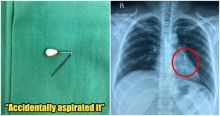

Tak Sengaja Menelan Pin Jilbab, Hal Mengerikan Ini yang Terjadi Pada Seorang Wanita Asal Malaysia Kesehatan - 20 Dec 2019, 14:56